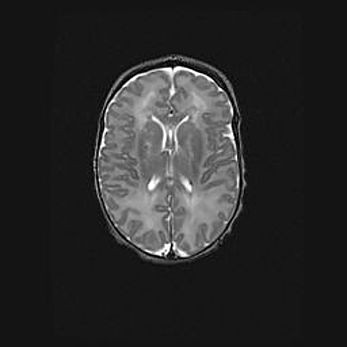

Сообщающаяся гидроцефалия. Кистозная энцефаломаляция головного мозга.

Возраст: 3 месяца 4 дня

Вес: 3100 г

Пол: женский

Окружность головы: 34 см

Срок гестации: 31 неделя

Кистозная энцефаломаляция головного мозга - одна из форм поражения головного мозга в детском возрасте. Характеризуется возникновением множественных и распространённых кист в коре, белом веществе и подкорковых образованиях головного мозга у плодов, новорождённых и детей раннего возраста. Развитие кистозной энцефаломаляции связано с внутриутробной асфиксией и гипотонией, родовой травмой, тромбозом синусов, пороками развития сосудов, инфекциями, сепсисом и другими причинами. Наиболее значимые инфекционные агенты: вирусы простого герпеса, цитомегалии, краснухи, токсоплазмы, энтеробактерии, золотистый стафилококк и другие.